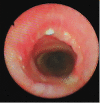

We report a case of primary tracheal schwannoma in a 31-year-old woman. She had a previous history of follicular thyroid carcinoma treated surgically and Turner syndrome. In a follow-up computed tomography scan, we found a partially obstructing intraluminal tracheal tumor, which was confirmed by bronchoscopy. The patient was treated by surgical resection and primary tracheal anastomosis. The tumor was 14 mm in diameter, with an intact capsule. Histologic analysis revealed a Schwann cell origin tumor.